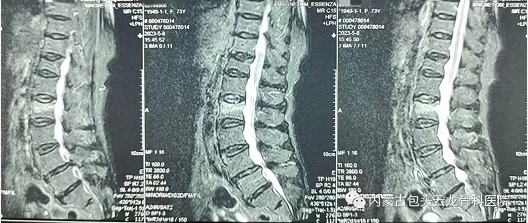

▲图为患者术前影像

手术患者74岁,女性,入院前无明显诱因出现腰背部疼痛,活动受限。手术前经检查患者患有骨质疏松症以及T12、L2椎体压缩性骨折,通过与患者的详细沟通与交流以及全面专业的病情评估,建议为患者实施机器人辅助下经皮椎体成形术,并针对骨科手术机器人功能、应用范围等进行科内术前讨论,将术中规划和操作注意事项作了详细说明。为患者制定个性化的手术方案,施行机器人辅助下的T12、L2经皮椎体成形术。